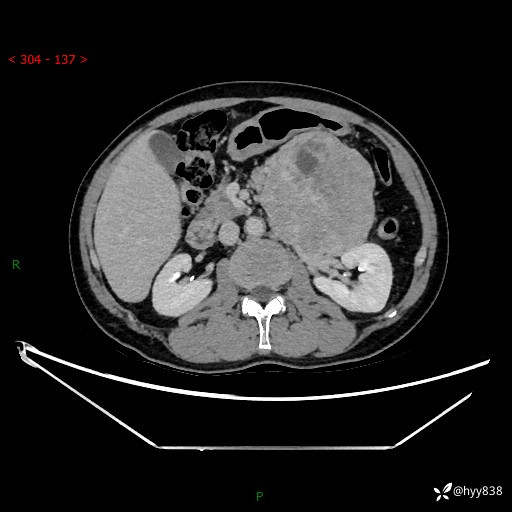

年龄:61岁

主诉:发现腹膜后肿瘤3天

腹部CT平扫+增强(动脉期+静脉期)